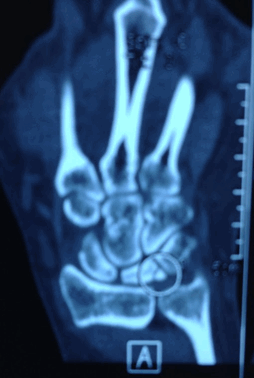

На компьютерной томографии были признаки фрагментации полулунной кости.

Пациентка 26 лет пришла на прием с болью в запястье. До нашей встречи жалобы были уже больше полугода. К моменту осмотра болезнь Кинбека была уже диагностирована, разрушение полулунной кости отчетливо видно на рентгене, стадия 3б.